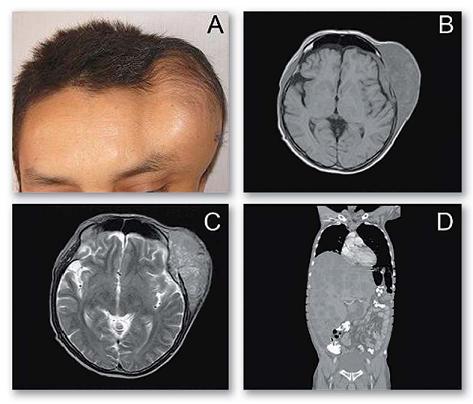

Posterior a la cirugía, el paciente no se realiza ningún tratamiento. Veintiocho meses después, presenta crecimiento progresivo de masa en región frontoparietal izquierda del cráneo. En la tomografía de cráneo se observa una masa de aspecto neoplásico a nivel de la calota que compromete el hueso frontal y parietal izquierdo, con signos de edema del parénquima cerebral ipsilateral de 10 x 6 x 8 cm de diámetro. La resonancia magnética evidenció áreas hiperintensas e hipointensas, sugiriendo sangrado y calcificaciones. En la gamagrafía ósea se halló una lesión hipercaptante localizada en la región parieto-temporal izquierda sin otras lesiones óseas metastásicas. La tomografía de abdomen mostró hígado aumentado de tamaño con presencia de múltiples lesiones metastásicas que reemplazan casi la totalidad del parénquima, sin evidencia de tumor residual en el área quirúrgica previa (figura 2).

Figura 2. Imagen de masa en región fronto-parietal izquierda (A). Resonancia magnética, en T1 y T2 se observa lesión heterogénea, con áreas hiperintensas e hipointensas, sugiriendo sangrado y calcificaciones (B y C). Tomografía de abdomen en la cual se identifica hígado aumentado de tamaño con presencia de múltiples lesiones metastásicas que reemplazan la casi totalidad del parénquima, sin evidencia de tumor residual en el área quirúrgica previa (D).